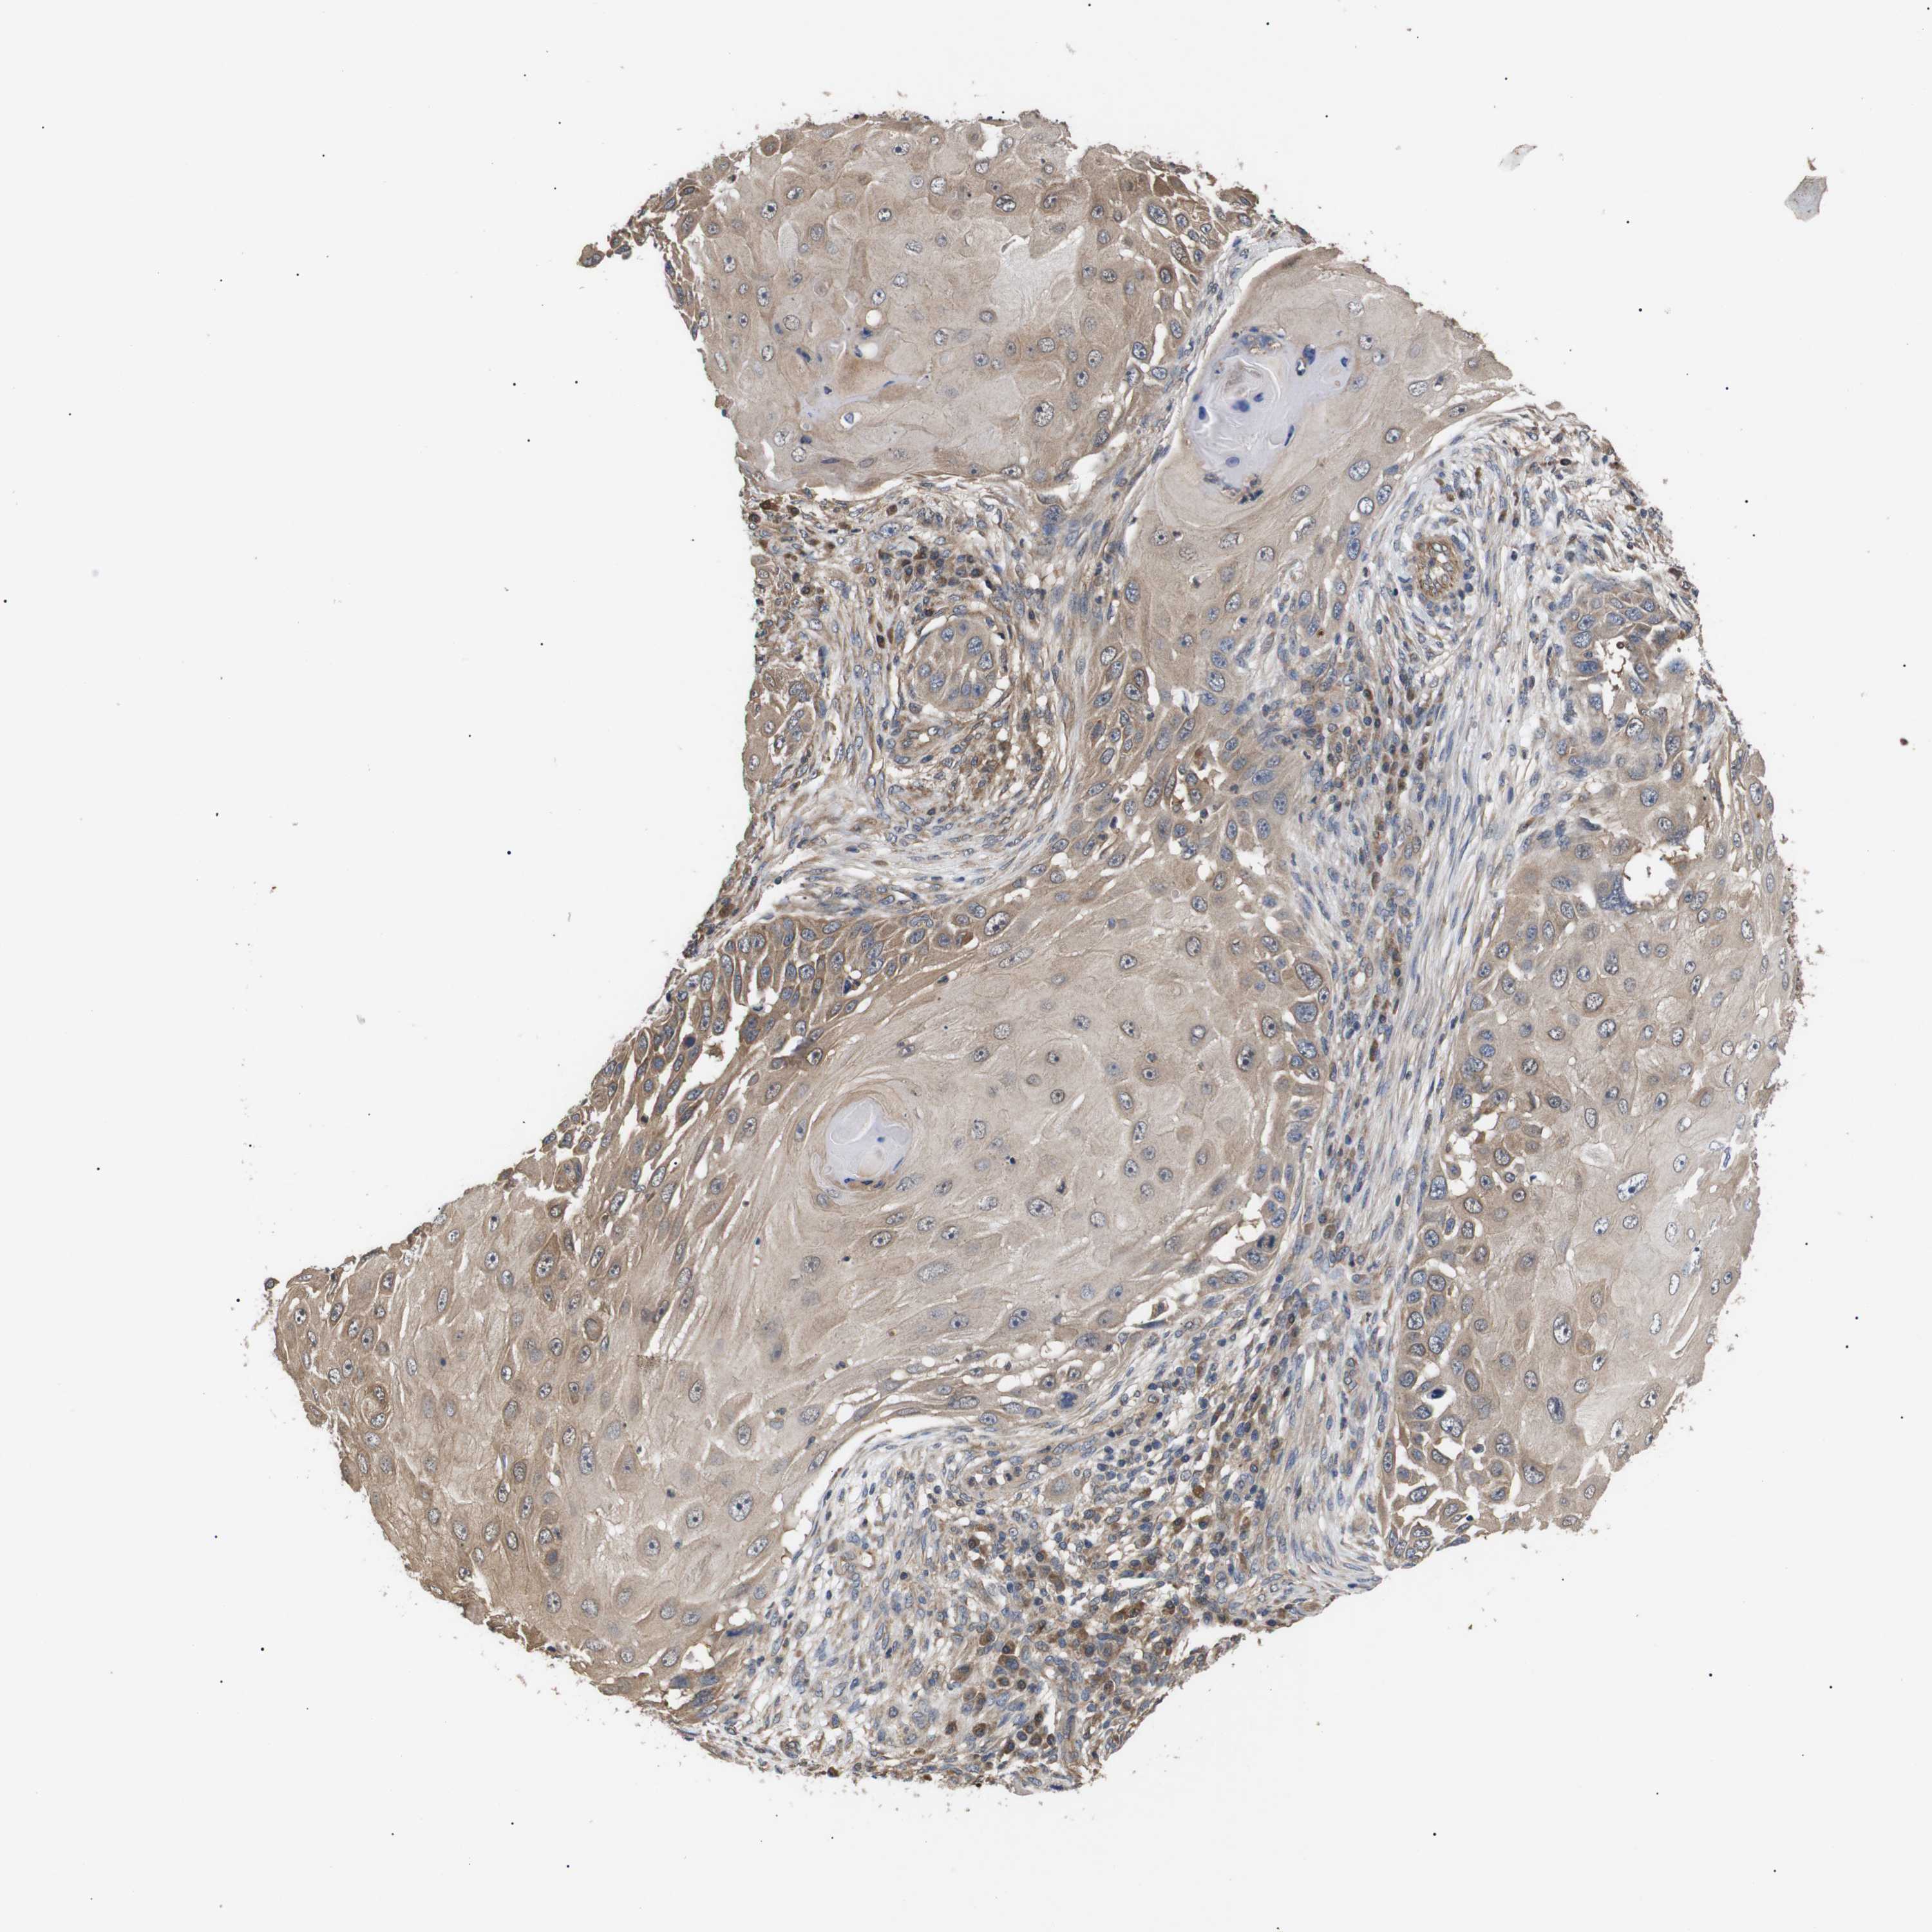

SKIN CANCER - Protein expressioni

A mouse-over function shows sample information and annotation data. Click on an image to view it in a full screen mode. Samples can be filtered based on level of antibody staining by selecting one or several of the following categories: high, medium, low and not detected. The assay and annotation is described here.

Antibody stainingi

Antibody staining in the annotated cell types in the current human tissue is reported as not detected, low, medium, or high, based on conventional immunohistochemistry profiling in selected tissues. This score is based on the combination of the staining intensity and fraction of stained cells.

Each image is clickable and will lead to virtual microscopy that enables deeper exploration of all samples and also displays staining intensity scores, fraction scores and subcellular localization as well as patient and tissue information for each sample.

Antibody CAB010162

Antibody CAB025656

Staining

High

Medium

Low

Not detected

Intensity

Strong

Moderate

Weak

Negative

Quantity

>75%

75%-25%

<25%

None

Location

Nuclear

Cytoplasmic/membranous

Cytoplasmic/membranous,nuclear

Squamous cell carcinoma, NOS

Basal cell carcinoma

Squamous cell carcinoma, metastatic, NOS